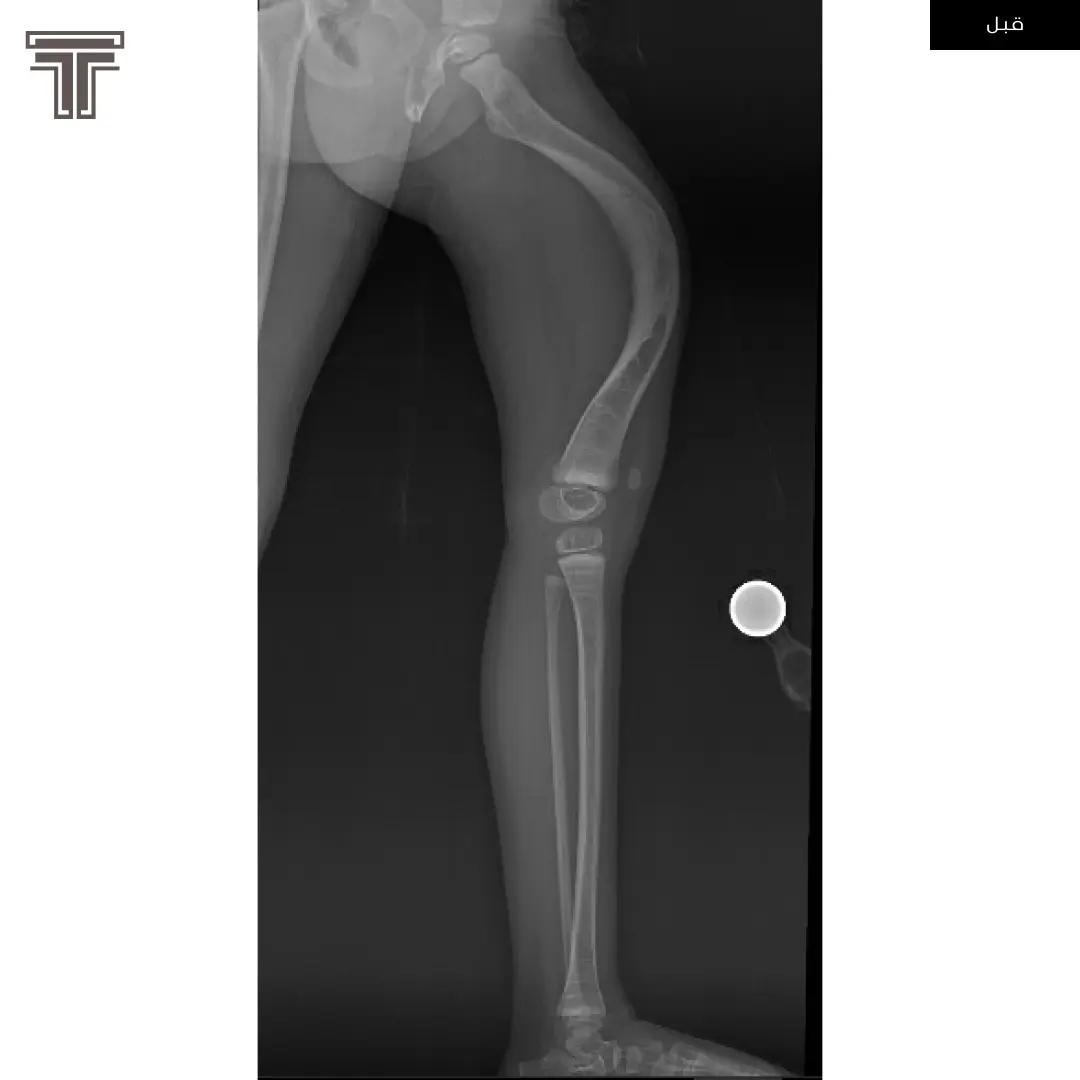

عندما تهمل خلوع الورك الولادية لعمر كبير يصبح علاجها وارجاعها صعب ويتطلب عملية استبدال للمفصل. وفي مثل هذه العمليات وتحديدا في استبدال مفاصل خلوع الورك الولادية يتطلب تقصير في طول الفخذ لتجنب المضاعفات.